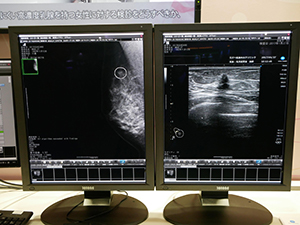

このほか,ブース内には女性医療のコーナーを設置。画像診断ワークステーション「NEOVISTA I-PACS MAMMO SERIES」のCAD機能を用いた乳がん診断のソリューションのデモンストレーションを行った。

●女性医療:NEOVISTA I-PACS MAMMO SERIESや小線源治療アプリケーター「SAVI」など検診から治療までのソリューションを紹介

女性医療のコーナーでは,乳がん検診から精査,治療までの流れの中で同社が提供する製品の紹介を行った。「I-PACS CX マンモビューワライセンス」と「I-PACS EX マンモオプション」をラインアップするNEOVISTA I-PACS MAMMO SERIESは,高速表示を特長とするワークステーション。超高精細画像でもスピーディに表示し,ストレスを感じさせない。読影者に併せて画面レイアウトを設定するハンギングプロトコールを採用したほか,微小石灰化クラスタと腫瘤陰影を検出するCADシステム「NEOVISTA I-PACS CAD typeM」と組み合わせて運用できる。ブース内では,超音波併用乳がん検診におけるCADの活用について,武部晃司氏(たけべ乳腺外科クリニック)が取り組んでいる“CAD navigated US screening”のビデオが上映された。

乳がん検診での診断を支援する |